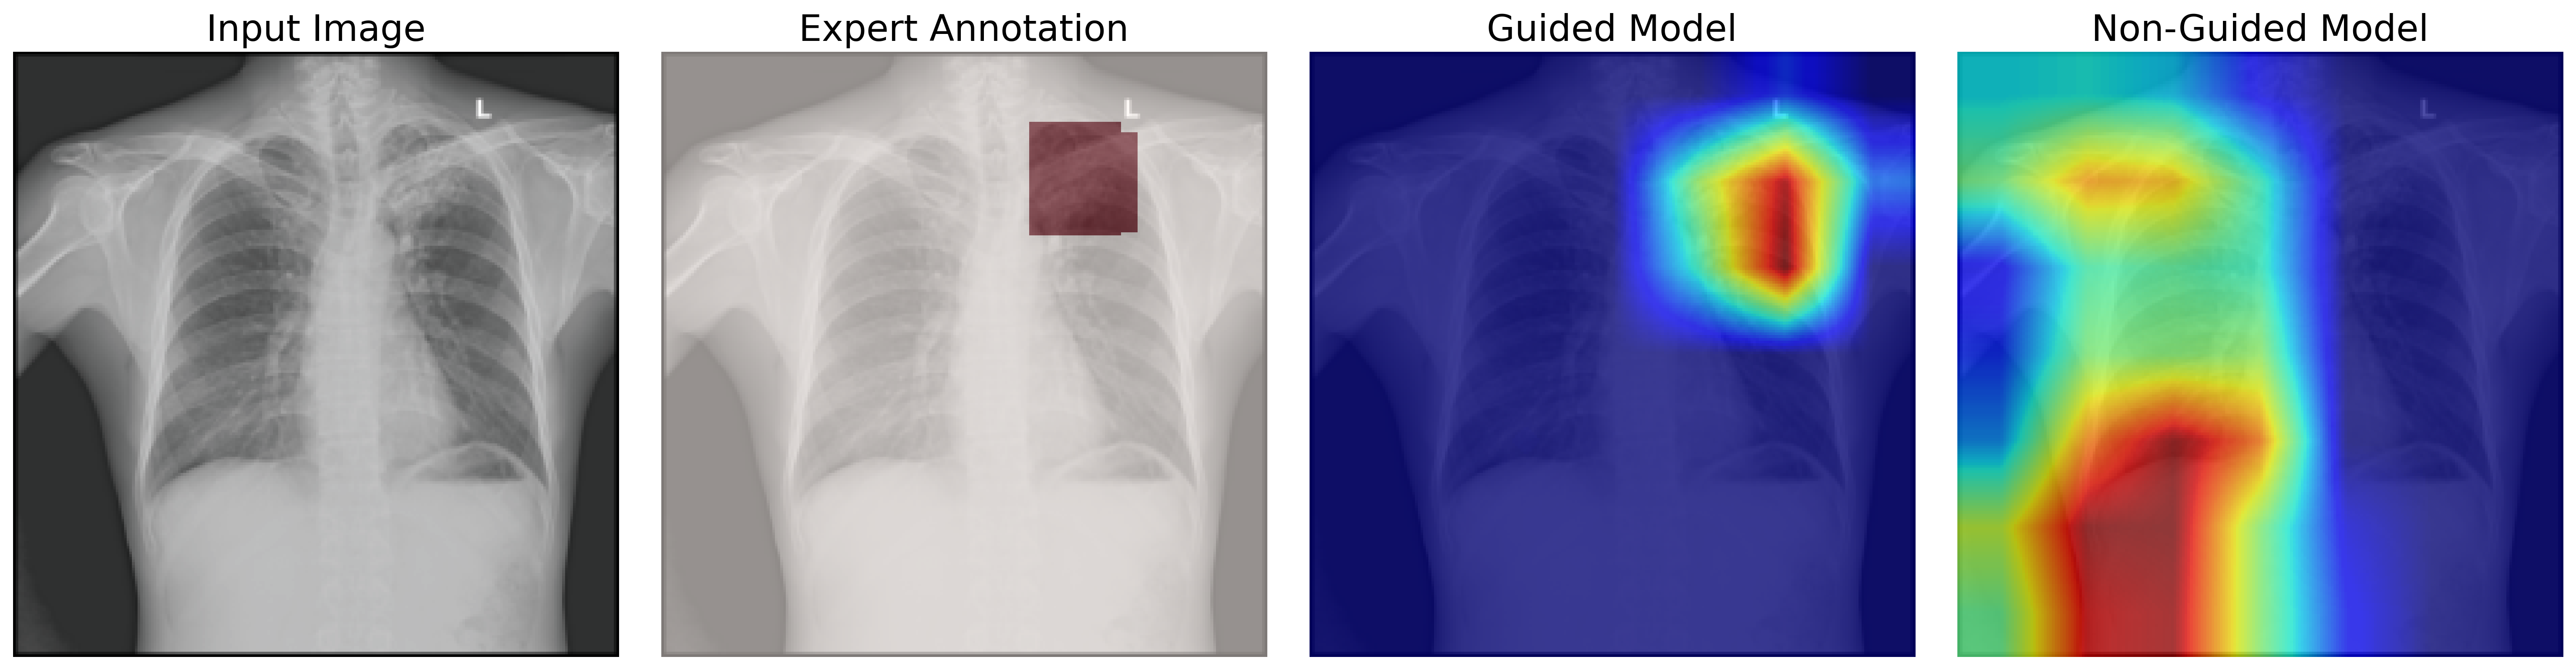

where is a hyperparameter controlling the strength of explanation-based supervision. Minimizing encourages the model to achieve both high classification accuracy and clinically-aligned attention patterns. As illustrated in Figure 1, our EGxFSL framework produces models that are both accurate and interpretable, particularly important in low-data environments where overfitting to irrelevant features is a common risk.

5.5 Interpretability Analysis

We qualitatively compare the guided and non-guided models using Grad-CAM visualizations. Figure 4 illustrates examples from the BraTS, VinDr-CXR, and SIIM-COVID datasets. The non-guided model predominantly focuses on irrelevant regions of the image, showing poor alignment with expert annotations. This misalignment undermines clinical trust in the model, even when classification accuracy is high.

In contrast, the guided model, trained using our proposed EGxFSL framework, consistently focuses on diagnostically meaningful regions of the image. This improved alignment with expert-defined areas enhances the interpretability and trustworthiness of predictions and contributes to better classification performance.